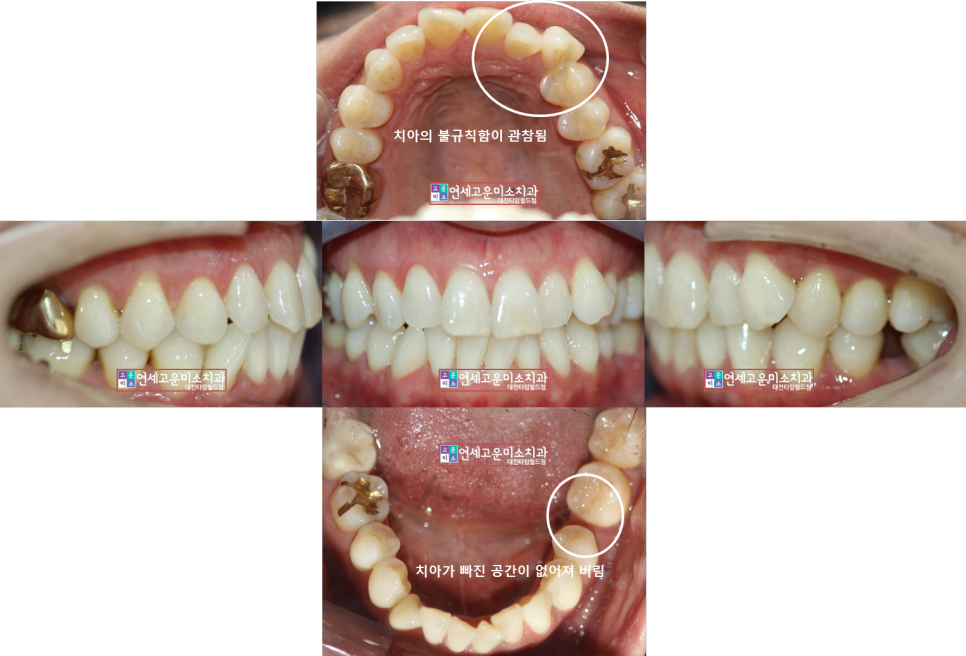

비발치 케이스) 덧니도 심하고 치아가 빠졌는데

공간이 없어져서 임플란트를 할 수가 없어요

근데 안 보이는 장치로 교정하고 싶어요.

40대 환자분이셨습니다

입은 돌출되지 않으셨고

덧니와 왼쪽 아래 치아 상실 후 공간이 없어져서

임플란트를 심을 수 없다는

이유로 내원하셨습니다.

덧니가 심하고 특히 왼쪽 아래는 공간상실이

너무 많이 진행돼서

임플란트를 할 수 없었습니다

교정 후 모습입니다

덧니도 해소하였고 임플란트 공간도 충분히

확보하여 옆 치아를 삭제하지 않고

마무리하였습니다.

기간은 2년 정도 소요되었습니다.